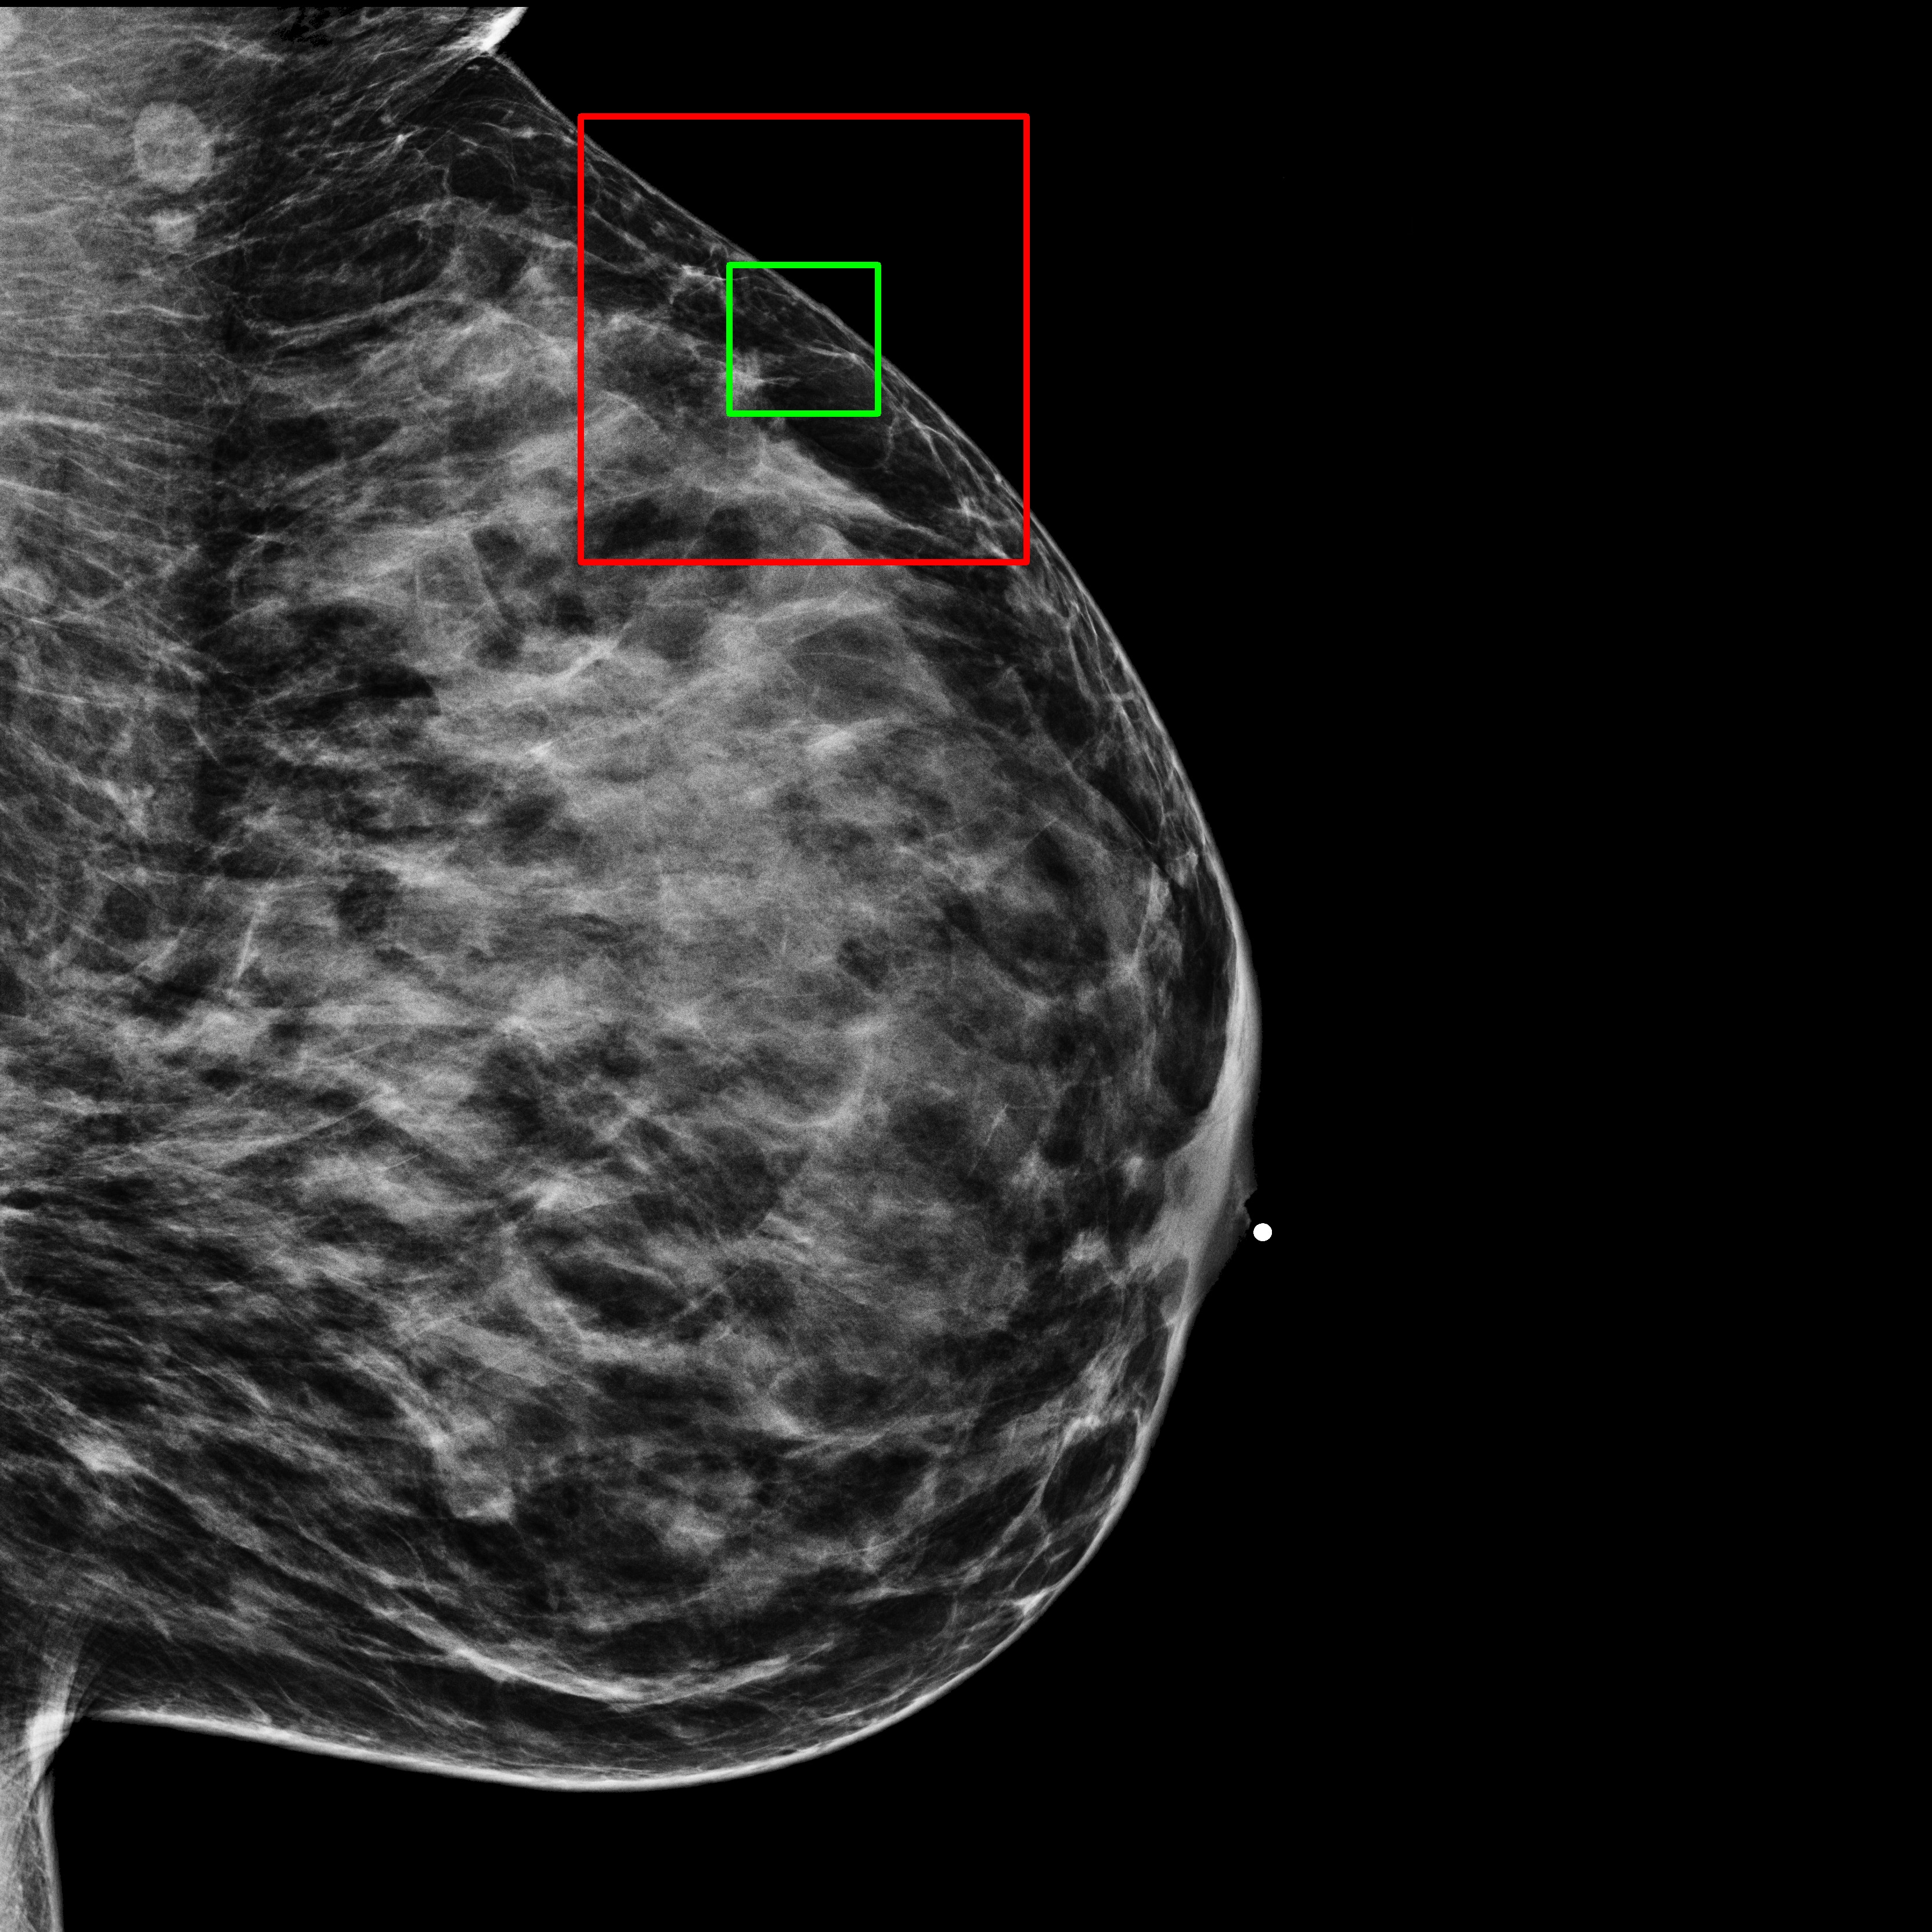

4.1.3 Qualitative Results

The baseline for this task is a single-channel U-Net-based DDPM trained on full-resolution -pixel patches extracted from mammograms. This model learns patch characteristics but performs poorly in image reconstruction tasks. Even if the patch is not generated from pure noise but from the partially noisy patch of an original image, the reconstruction is poor, as shown in Fig. 3(c).

What MAMBO can achieve in terms of qualitative results is presented in Fig. 1 and Fig. 3(d). MAMBO is able to generate high-quality images that are visually indistinguishable from the originals, representing plausible mammogram data to layman eyes. Results are also validated with expert radiologists, with quantitative results shown in Sec. 4.2.

Fig. 3(d) illustrates what MAMBO can achieve in terms of whole mammogram generation. When using global and local context data extracted from an original image, the denoised image (Fig. 3(b)) is difficult to distinguish from the original (shown in Fig. 3(a)). When providing only the original global context and generating local context and target patches from noise, we still observe good results, as we show in Fig. 3(d).